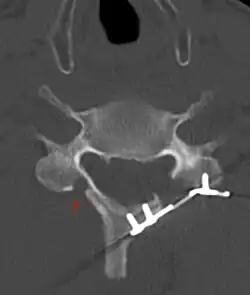

![]() CT scan of Laminoplasty of cervical vertebra | |

Laminoplasty is an orthopaedic/neurosurgical surgical procedure for treating spinal stenosis by relieving pressure on the spinal cord. The main purpose of this procedure is to provide relief to patients who may have symptoms of numbness, pain, or weakness in arm movement. The procedure involves cutting the lamina on both sides of the affected vertebrae (cutting through on one side and merely cutting a groove on the other) and then "swinging" the freed flap of bone open thus relieving the pressure on the spinal cord. The spinous process may be removed to allow the lamina bone flap to be swung open. The bone flap is then propped open using small wedges or pieces of bone such that the enlarged spinal canal will remain in place.